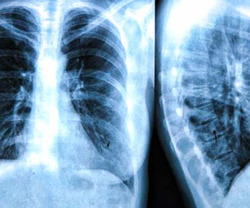

Las manifestaciones clásicas de la fibrosis quística son: el compromiso de vía aérea superior (sinusitis, poliposis), pulmonar (infección con microorganismos típicos), tos y expectoración crónica. Los hallazgos habituales en la radiografía y tomografía de tórax son: bronquiectasias, tapones mucosos, atelectasias, hiperinsuflación. A nivel gastrointestinal y nutricional: ileo meconial, prolapso rectal, síndrome de obstrucción intestinal, insuficiencia pancreática, pancreatitis recurrente, cirrosis biliar. Todo esto con lleva a malnutrición, déficit de proteínas y vitaminas.

Imagen ilustrativa.